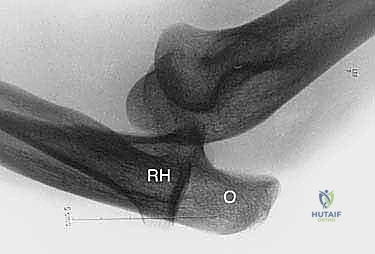

- الأشعة السينية (X-rays): لاستبعاد وجود كسور قديمة، تكلسات في الأربطة، أو تشوهات عظمية مثل الكوع الأفحج. في بعض الأحيان، قد تظهر الأشعة تكلساً صغيراً عند منشأ الرباط (علامة أوزبورن-كوتريل).